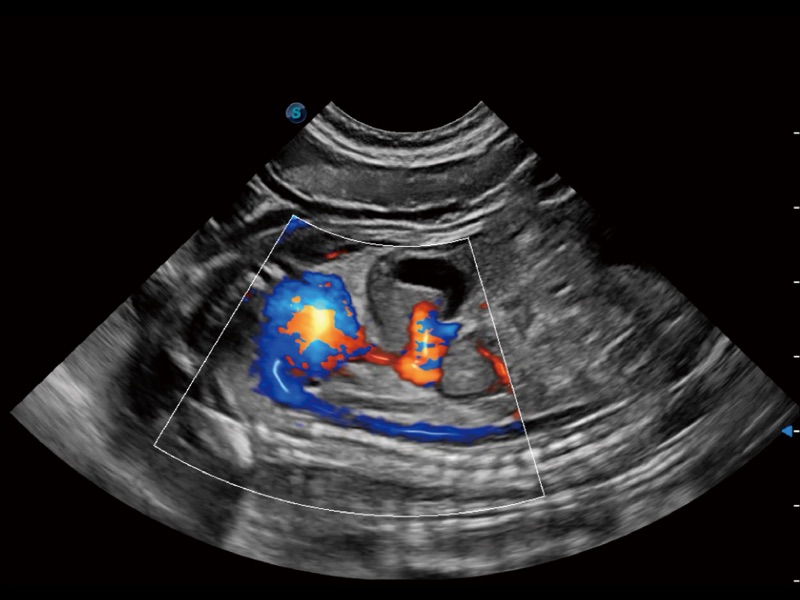

优异的基础图像

ProPet 70 全新的动物超声智能软件和丰富的探头群,为动物医生提供了高清晰度和精细分辨率的图像,无论在宠物、马科、畜牧还是实验室动物等应用中都可以轻松应对,为您的日常工作带来满意的体验。

(犬)胎儿主动脉弓立体血流